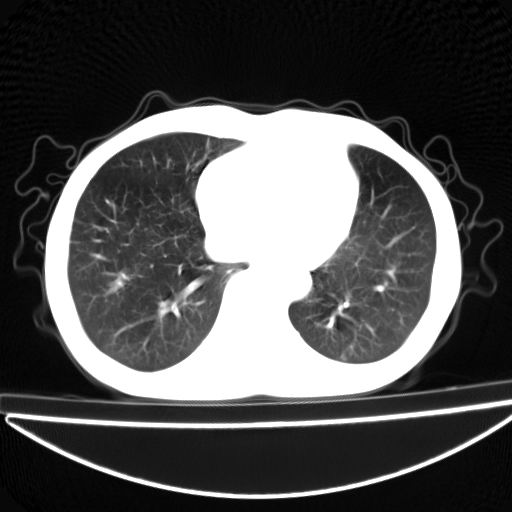

以下是引用杀毒软件在2009-4-28 17:58:00的发言:[br]考虑----左肺慢性肺脓肿形成继发上叶含气不良---抗炎后复查---待排肿瘤所致[br][br][本贴已被 杀毒软件 于 2009-4-28 18:01:26 修改过]